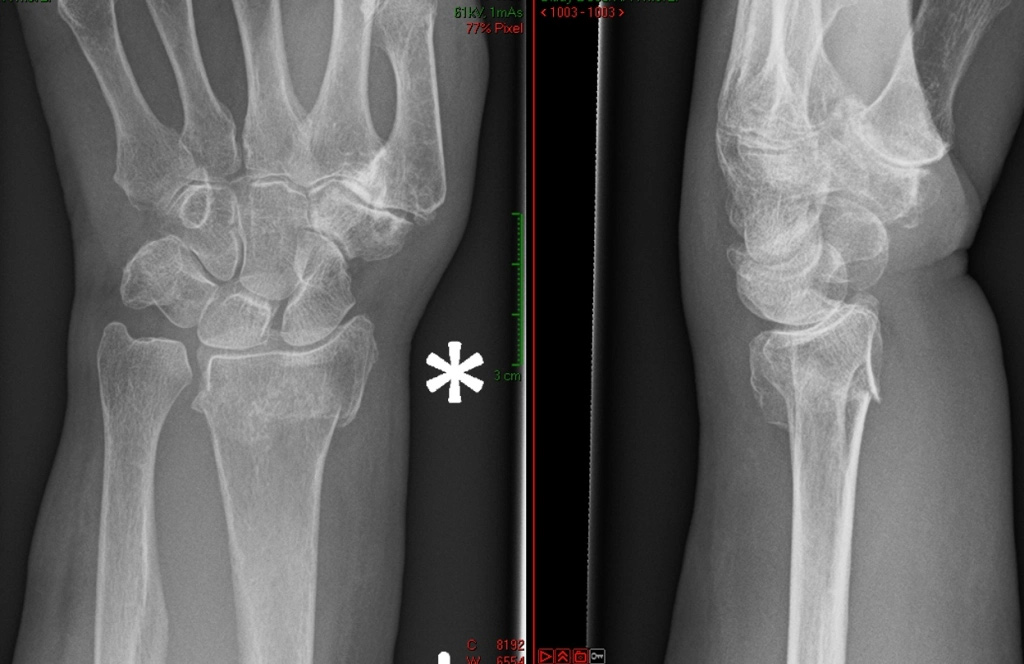

Common symptoms of a wrist fracture include immediate and intense pain, swelling, bruising, and tenderness around the affected area. Diagnosis typically involves a physical examination followed by imaging tests such as X-rays to determine the extent and nature of the fracture.

When a distal radius fracture is complex or unstable, surgical intervention is often required to ensure proper healing. Several surgical options are available, each with specific indications and advantages.